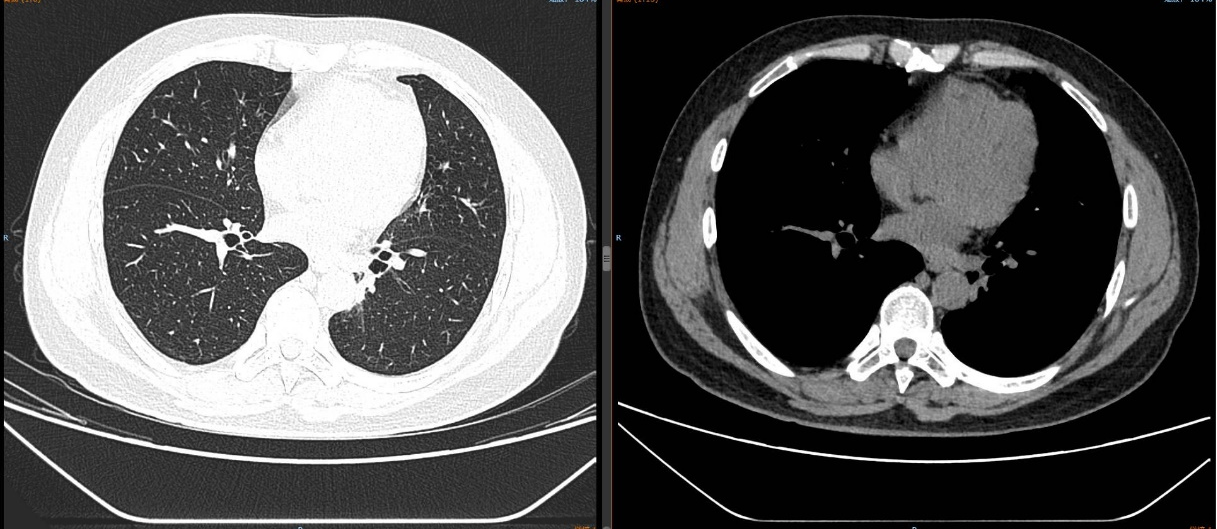

治疗5个月后(2025-05-07):复查CT显示左肺病灶显著缩小,达到PR,肺内结节明显吸收。

截至目前,PFS已超过10个月,病情持续稳定。